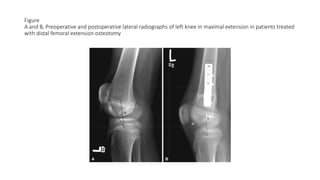

Figure

A and B, Preoperative and postoperative lateral radiographs of left knee in maximal extension in patients treated

with distal femoral extension osteotomy